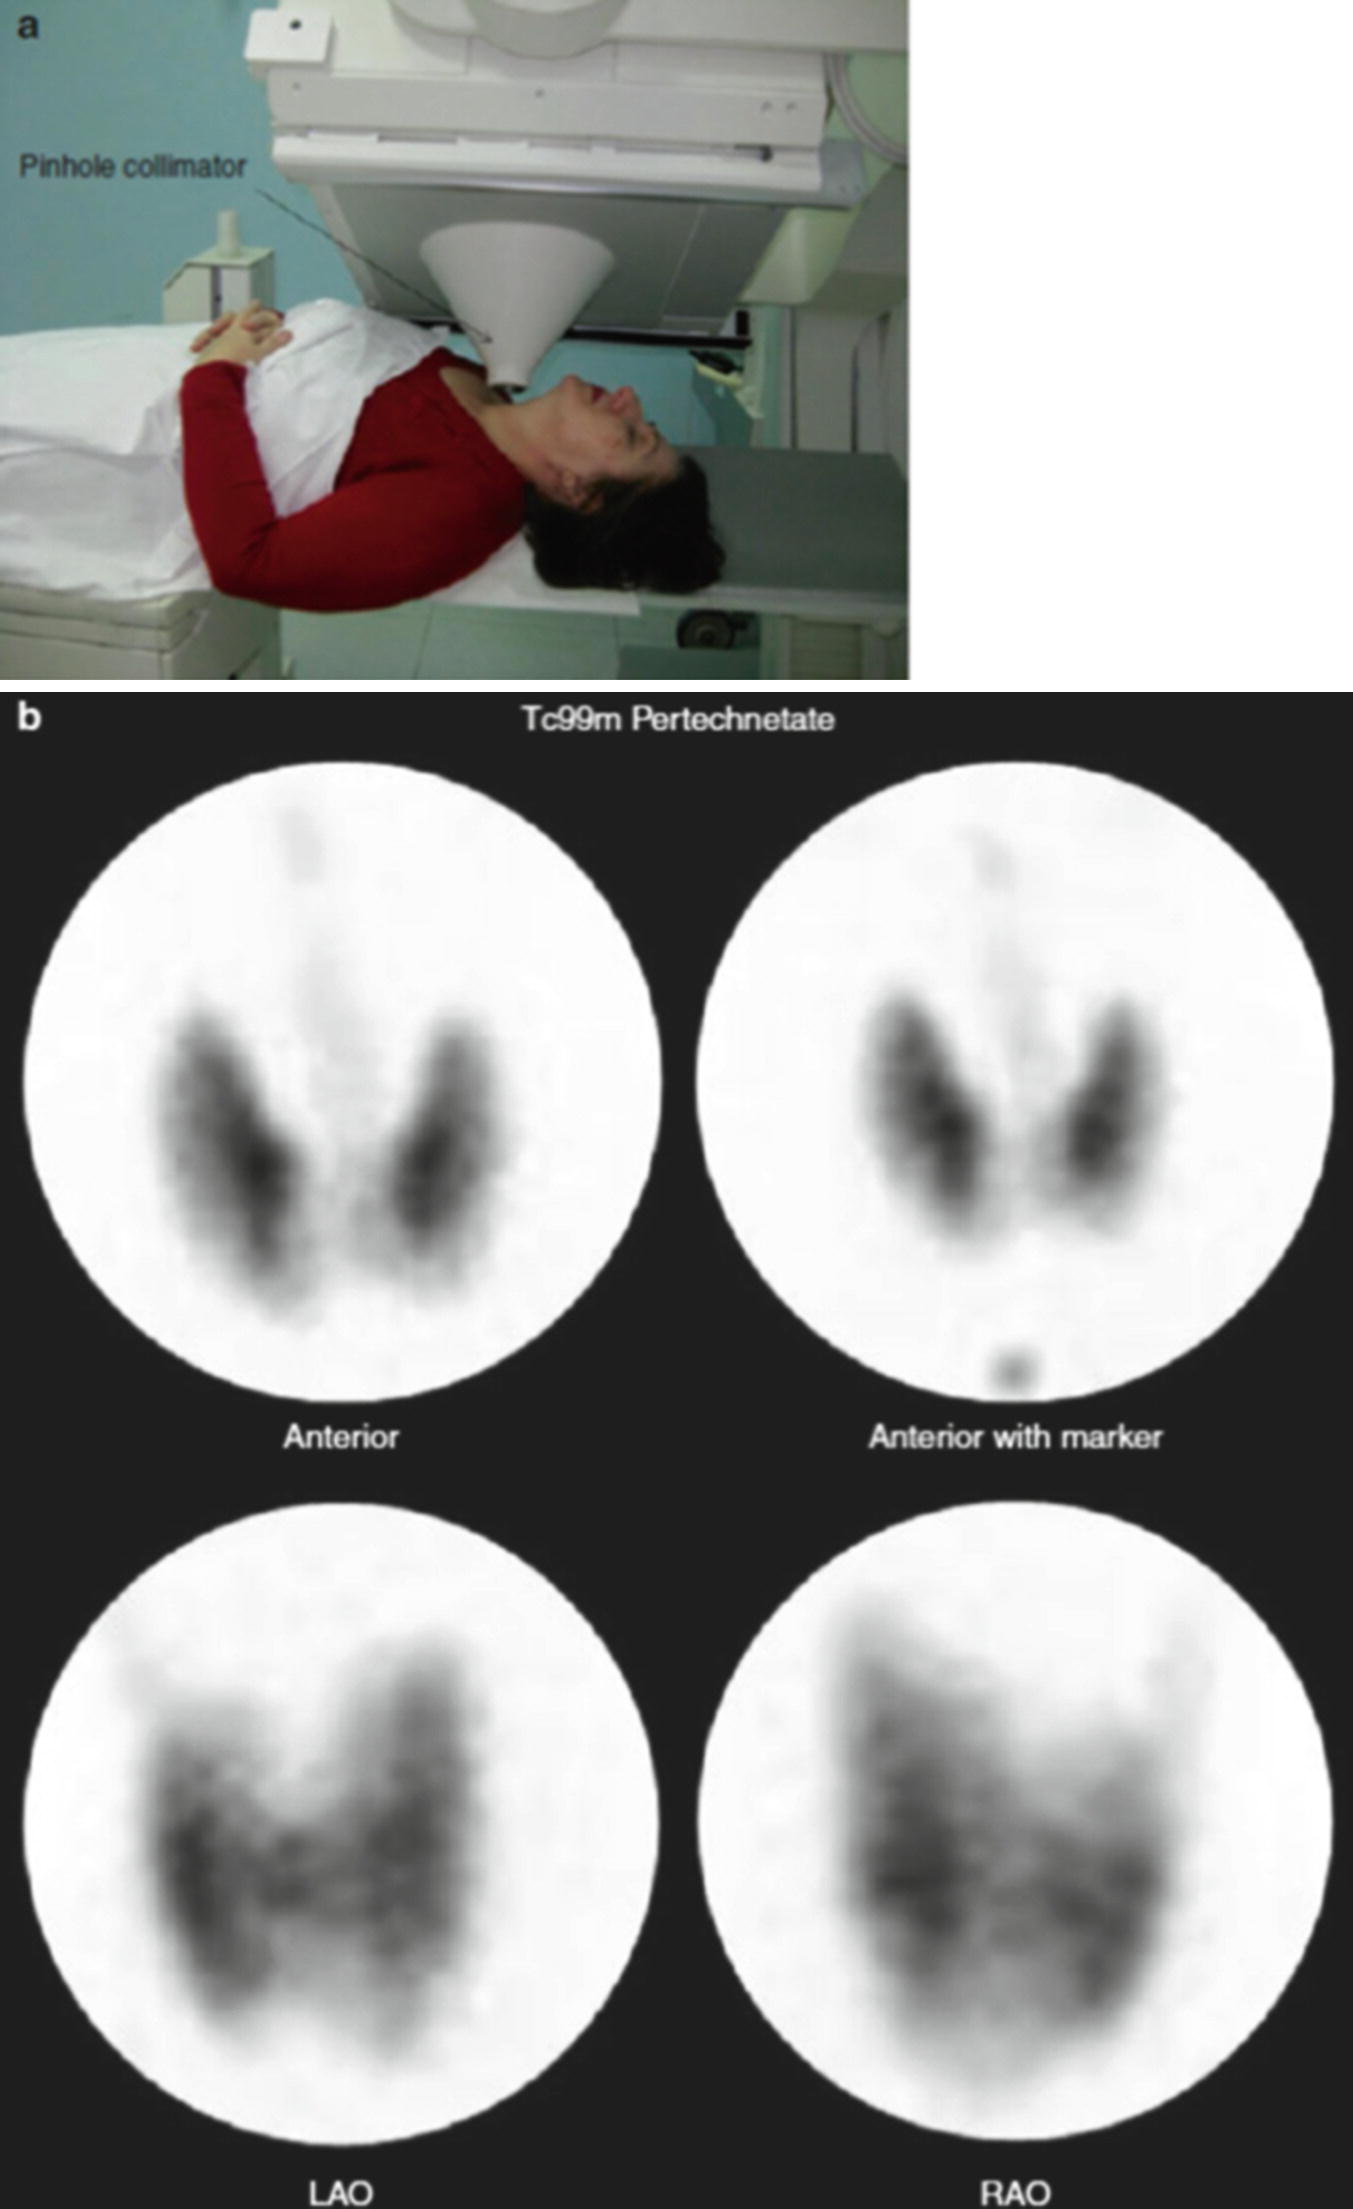

A And B Nuclear Medicine Study Images Of The Patient In Case 5 Download Scientific Diagram